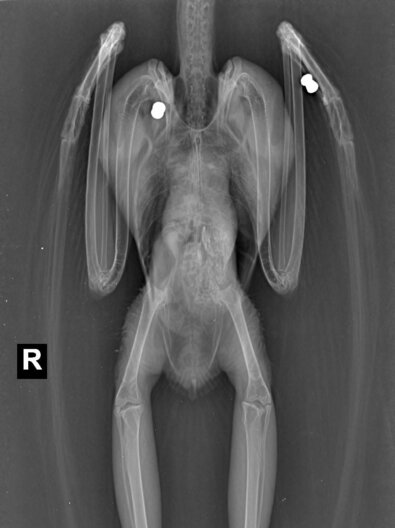

Im Rahmen der Eingangsuntersuchung in der aktion tier Wildtierstation wurde die Eule durch Tierärztin Karolin Schütte geröntgt und dabei festgestellt, dass zwei Luftgewehrprojektile – sogenannte „Diabolos“ – im Körper der Schleiereule steckten. In einer anschließenden Operation wurden die Projektile entfernt. Unter anderem wurden Knochen der linken Handschwinge verletzt und das rechte Schulterblatt durchschlagen. Bis Anfang Mai blieb die Schleiereule bei uns in der Station und konnte dann vollständig genesen wieder ausgewildert werden.